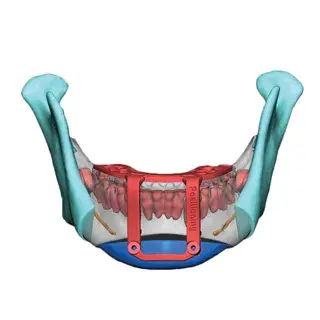

3D Systems' VSP® surgical planning solutions for craniomaxillofacial (CMF) applications received FDA clearance as a service-based approach to personalized surgery over 10 years ago.

3D Systems and Stryker Corporation have partnered to provide surgeons with best-in-class products and services for craniomaxillofacial surgeries. As a leader in personalized healthcare solutions, 3D Systems has planned and delivered devices for more than 140,000 patient-specific cases. The Stryker Craniomaxillofacial business specializes in providing patient-specific options and innovative solutions that help drive efficiencies in surgical suites. The combination of Stryker’s specialized team and advanced implants with 3D Systems' cutting-edge 3D printing technologies and expert consulting services positions both companies to provide a superior level of service to healthcare professionals who use these revolutionary solutions.